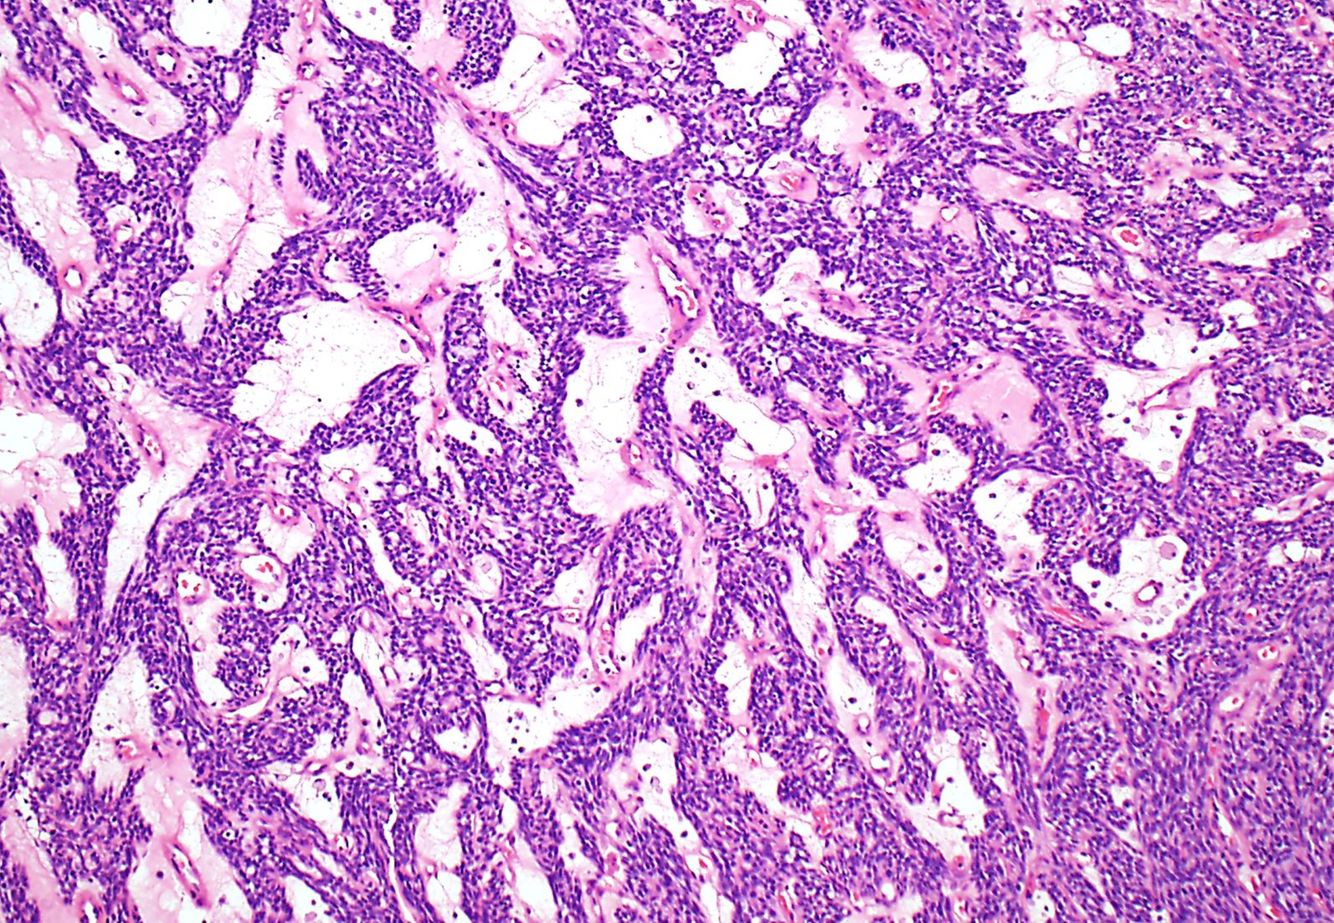

Thymoma perivascular spaces

xxxxxx

More commonly seen in type B thymomas.